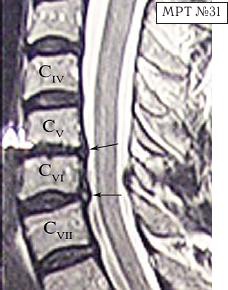

МРТ № 31 ![]() Он взял отпуск и поехал в Москву в довольно известную частную клинику. Прошёл курс лечения, который включал в себя «стандартный набор»: — мануальную терапию, с целью уменьшения (устранения) болевого синдрома, путём восстановления соотношений суставных поверхностей дугоотростчатых суставов в сегментах CV-CVI и CVI-CVII (устранение сублюксации); — массаж шейного отдела позвоночника (для расслабления мышц, улучшения кровообращения); — физиотерапию — магнитотерапию, инфракрасный лазер на воротниковую зону, с целью уменьшения воспалительных процессов и отёчности в поражённых тканях; — медикаментозную терапию — стандартный набор нестероидных препаратов, витамины и анальгетики; — физические упражнения на тренажёрах и лечебная физкультура для укрепления мышечного корсета позвоночника и выработки правильной осанки, придание связочно-мышечному аппарату необходимой гибкости с целью увеличения объёма движений в позвоночнике. После лечения действительно почувствовал себя лучше, работоспособность была восстановлена. Но, чтобы не утратить достигнутый результат лечения, следуя рекомендациям, полученным в московской клинике, он продолжил заниматься на тренажёрах. Даже приобрёл несколько универсальных (многофункциональных) тренажёров. Один установил дома, другой — на работе. Жизнь вошла в привычное русло. Боли в шее периодически возникали, но проходили после занятий на тренажёре. К медикаментам прибегал в редких случаях. Так продолжалось практически год, пока не появилась боль в левой руке и онемение IV и V пальцев. Занятия на тренажёре только усиливали боли, а лекарства практически не действовали. В связи с чем он был вынужден опять обратиться в ту же клинику. После лечения (практически по той же схеме) боли уменьшились, но полностью не прошли, онемение усилилось. Через некоторое время появилась субфебрильная температура (37–37,2 °C), общая слабость, частые головные боли, головокружения. По жалобам и ощущениям с его слов: «На голову надели будто тесную шапку и она сдавливает. А в голове туманность какая-то, мысли путаются, на чём-то сосредоточиться практически невозможно. Порой забываю, что минуту назад делал. Такое ощущение, что в голове полно посторонних мыслей: только от одних отделаюсь, как появляются другие» и так далее. Естественно, он вынужден был опять обратиться в медицинское учреждение, где ему повторно сделали МРТ (№ 32). ![]() После обследования у него было обнаружено: — абсолютный стеноз спинномозгового канала шейного отдела позвоночника с полным блоком ликворных путей и сдавлением дурального мешка спинного мозга на уровне сегментов CV-CVI и CVI-CVII; — в сегменте CV-CVI — значительный спондилёз, гипертрофия задней продольной связки, и практически компенсированная спондилёзом грыжа межпозвонкового диска; — в сегменте CVI-CVII — довольно активная грыжа межпозвонкового диска; — на уровне поражённых сегментов выраженный эпидурит. После данного обследования, когда врачи увидели грыжи межпозвонковых дисков, да и то, что происходило у пациента в шейном отделе позвоночника, они стали категорически настаивать на немедленной операции. Однако перспектива стать инвалидом на всю оставшуюся жизнь явно не прослеживалась в планах пациента. Когда прозвучали два слова — «грыжи» и «операция», этот человек, естественно, тут же вспомнил и про меня, и про нашу давнишнюю с ним дружбу. Однако меня не удовлетворили результаты его обследования. Если бы дело было только в грыжах, это полбеды. Меня смущало наличие других симптомов, которые косвенно свидетельствовали о возможном поражении ЦНС. Поэтому я послал его на дополнительные обследования МРТ головного мозга (№ 33), тесты (ИФА (иммуноферментный анализ), ПЦР (Полимеразная Цепная Реакция на инфекции), которые дали положительный результат на герпесвирусы: Epstein-Barr virus (EBV) (вирус Эпштейна-Барр) и Cytomegalovirus (CMV) (вирус Цитомегаловирус). МРТ № 33